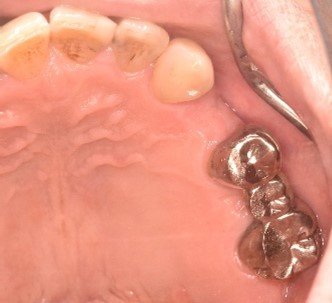

Before

赤丸は抜歯しました

【抜歯後】

【骨造成前】

【骨造成後】

After